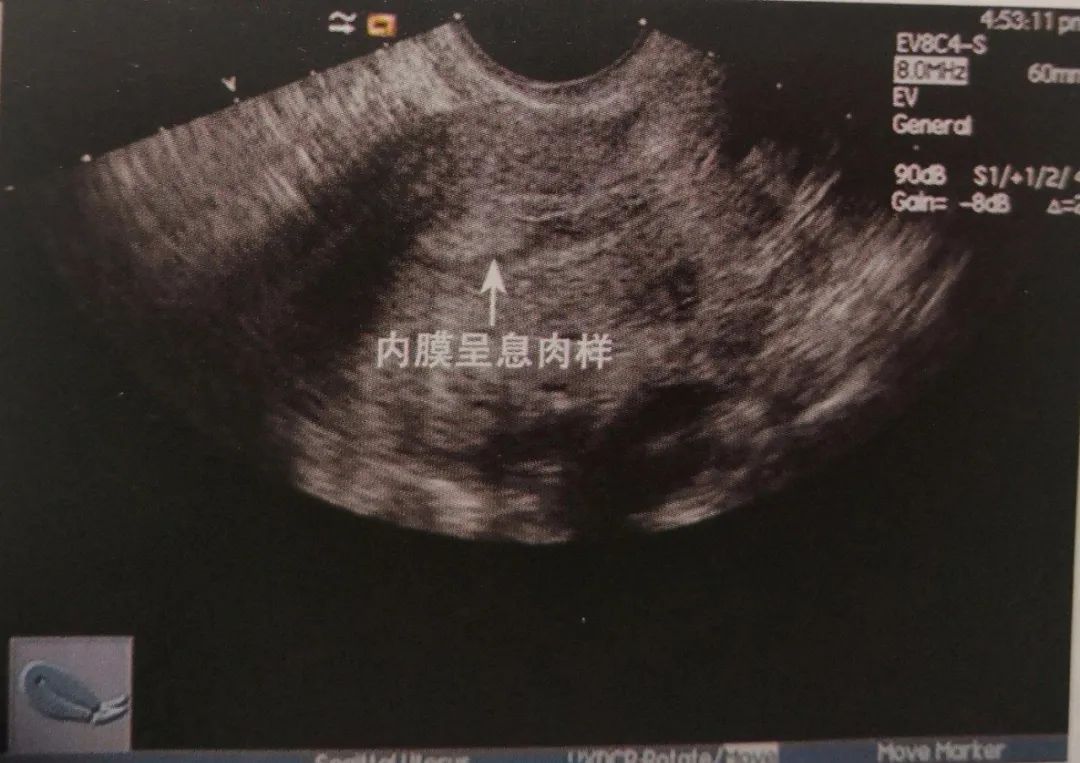

2、子宫内膜有病变,比如有子宫内膜息肉或者有黏膜下的小肌瘤,B超检查的时候可能会有回声不均的现象,一般都会伴有月经不规则出血的临床症状;

如果仍然是内膜回声欠均匀,应该考虑有子宫内膜息肉的可能,这时候需要做宫腔镜检查。在宫腔镜直视下看子宫内膜是否有异常,如果有异常要刮宫送病理,如果有息肉可以当时摘除。然后送病理,看看是否有子宫内膜病变或者是子宫内膜息肉,根据病理结果对症治疗。